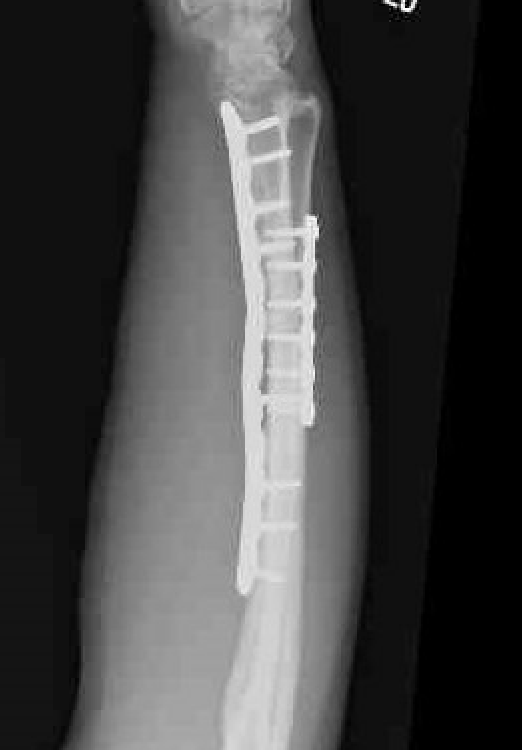

Radial malunion / Non anatomical ORIF of BBFF

Radial malunion after ORIF of BBFF

Etiology

Non operative management of BBFF

Non anatomical ORIF of BBFF

Bone loss radius

Radius short

Lengthening radius difficult

Ulna shortening

Radius angulated / rotated

Radial osteotomy

TFCC repair +/- TFCC reconstruction